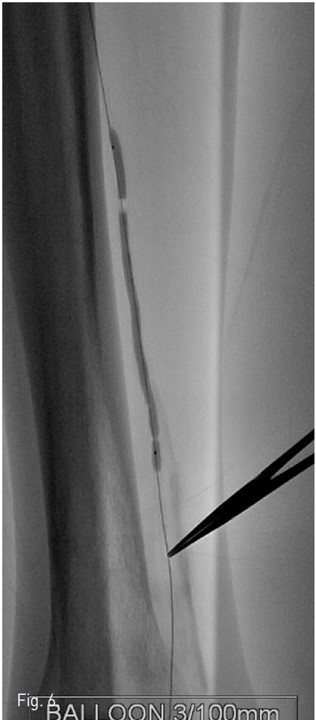

Fig. 6.

Fig. 6. Subintimal balloon angioplasty is performed at posterior tibial artery with a 3mm/10cm balloon. Note the balloon waist at distal portion of the inflated balloon catheter that is compatible to the location of calcification(retrograde wire passage point).